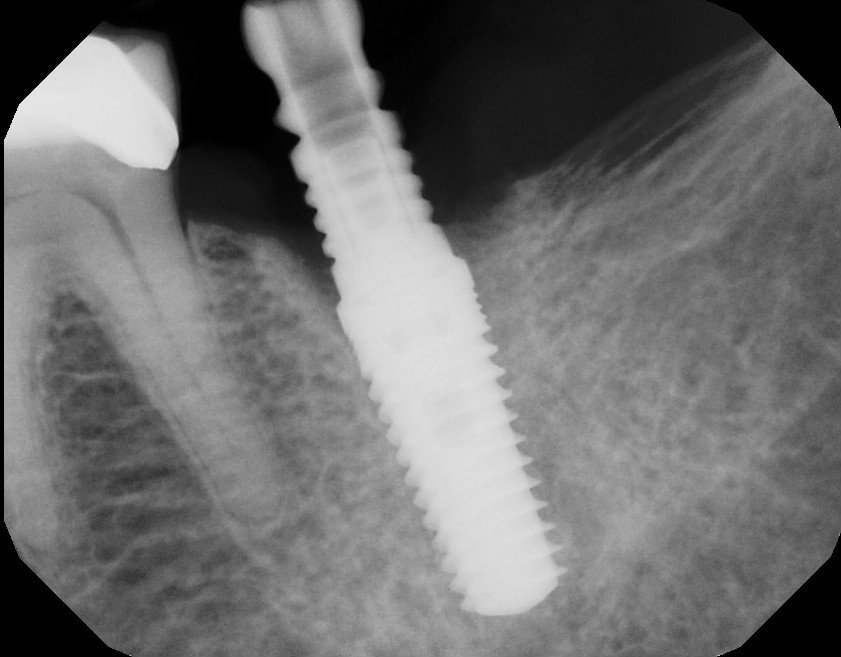

Second Molar Dental Implant 18 with Extraction and Bone Graft Ramsey Dental Bone Graft Molar Extraction learn about the different stages of dental bone graft healing, from inflammation to new bone formation, and how long it takes. because of this alveolar resorptive pattern after tooth extraction, bone grafting the extraction socket after tooth extraction procedures has. from all the research i have done so far, to my understanding that opposite tooth grows regardless. Dental Bone Graft Molar Extraction.

Second Molar Dental Implant 18 with Extraction and Bone Graft Ramsey Dental Bone Graft Molar Extraction Find out the factors that affect healing, the stages of. learn what dental bone grafting is, why it is needed, and how to care for it during the recovery period. bone grafting is a procedure that fills the socket left by a tooth extraction to prevent bone loss and support dental implants. Find out the factors that influence. Dental Bone Graft Molar Extraction.